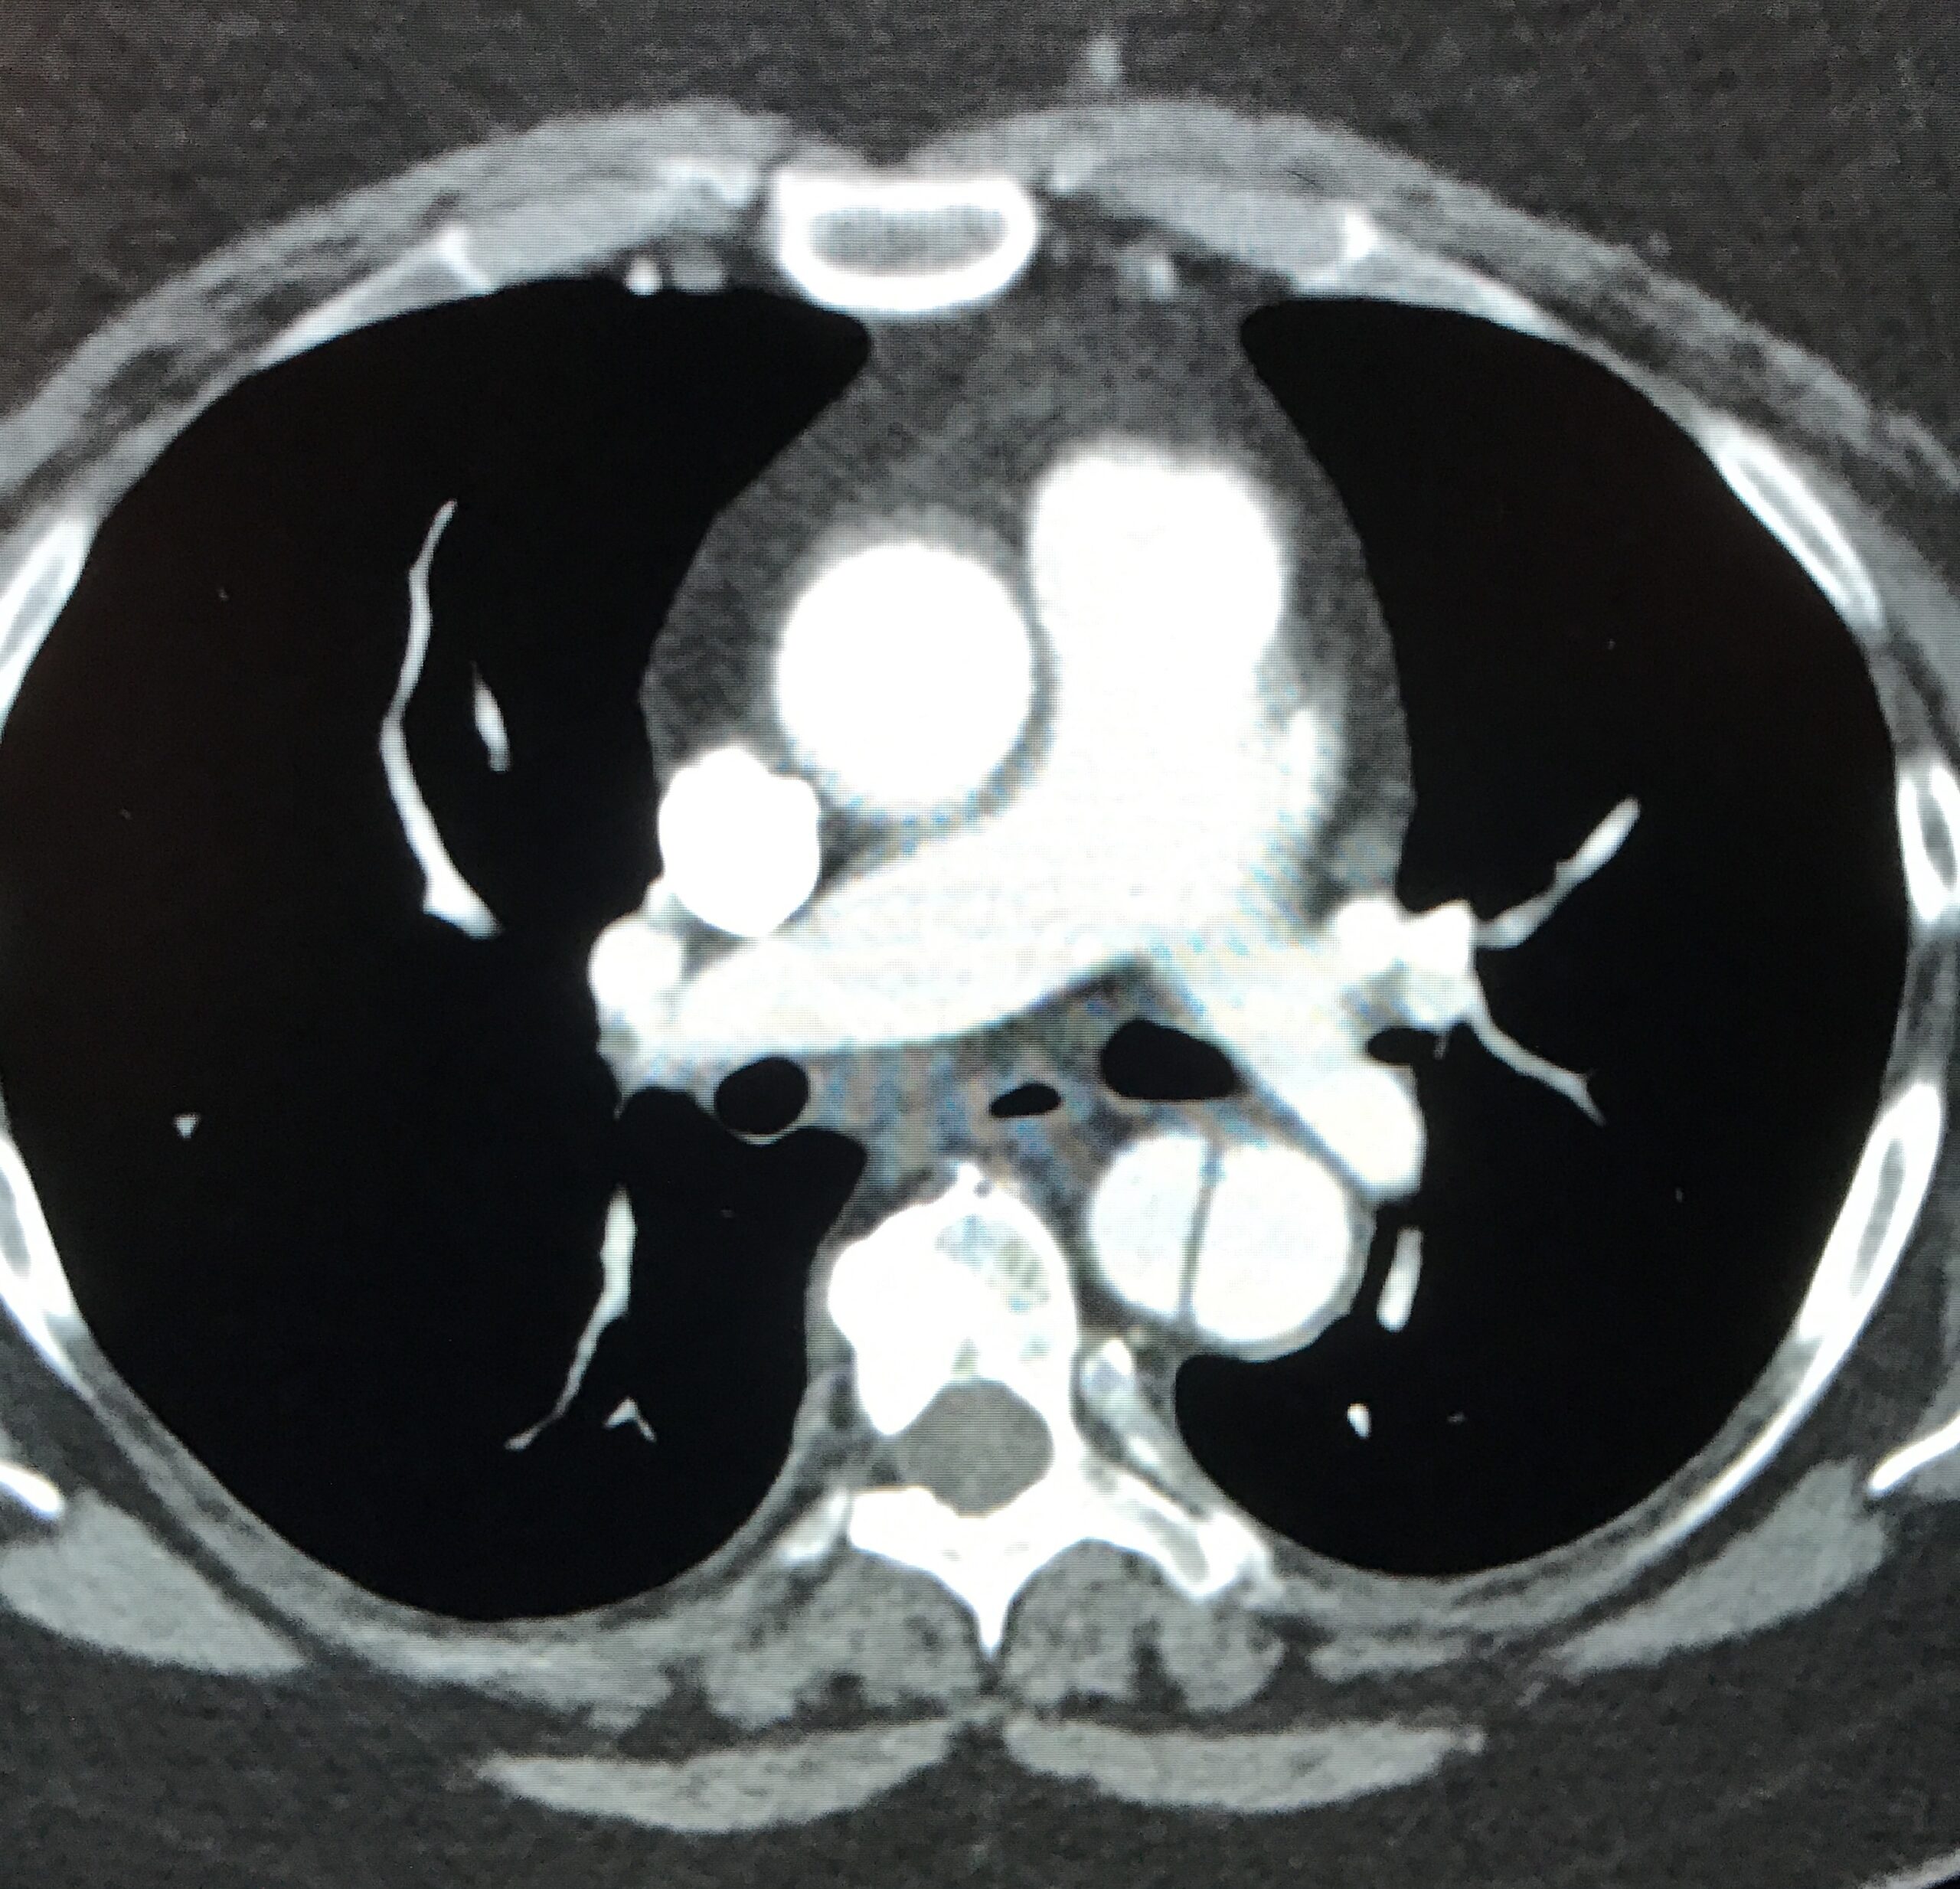

- The d-dimer returns markedly elevated.

- A CT pulmonary angiogram is ordered and results in the images below:

Image courtesy of Sam Ashoo, MD

Diagnosis: Acute Descending (Type B) Aortic Dissection

- The benefit of contrast: Though CT imaging has come a long way, the identification of vascular abnormalities continues to require the administration of intravenous contrast. As this case highlights, non-contrast imaging of the aorta relies on edema of surrounding structures or aneurysmal dilatation of the aorta to suggest abnormality. In the absence of either of these findings, no further analysis of the aorta can be made. The addition of contrast clearly highlights the intra-vascular space allowing for the correct diagnosis of this life threatening disease.